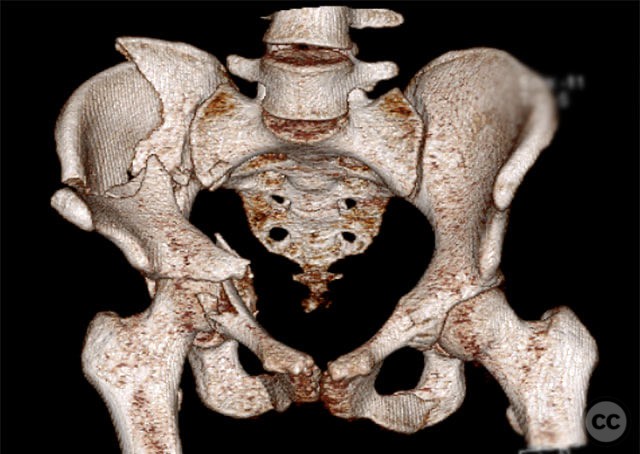

Clinical and radiological findings:  A 19-year-old female sustained a high-energy injury in a motor vehicle accident. Initial AP pelvic radiograph demonstrated a right-sided, displaced, comminuted associated both column acetabular fracture (AO/OTA 62C3), with a separate fracture fragment involving the greater sciatic notch (GSN). The right sacroiliac (SI) joint was incompletely disrupted. Surface rendered CT images confirmed the complex fracture morphology, including the separate GSN fragment and the SI-sacral injury, which rendered the typical posterior iliac fragment non-intact. Axial CT at the acetabular dome level revealed multiple displaced fragments and provided further detail regarding soft tissue involvement.